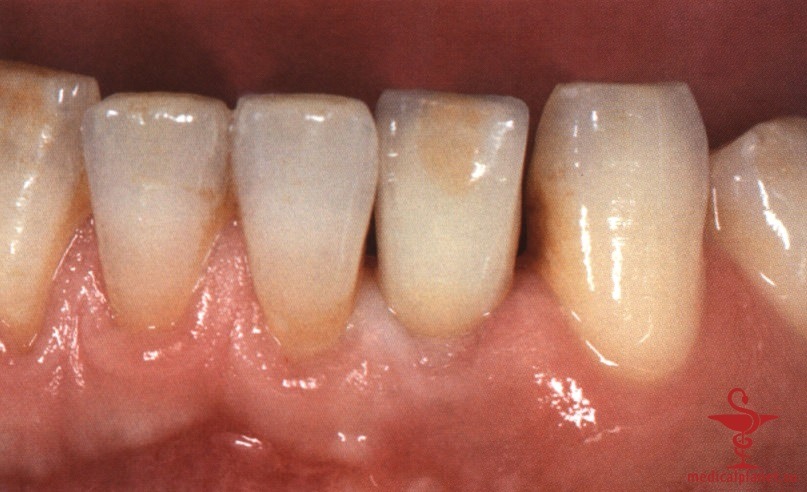

Сложность такого подхода обусловлена высокой вероятностью наличия или формирования костного дефекта в области имплантации. В течение многих лет считалось, что имплантат остеоинтегрируется только при минимальном зазоре между ним и костью. Однако в 1988 г. Carlsson и соавт. описали феномен «костного прыжка», который заключается в возможности достижения остеоинтеграции даже при довольно большом расстоянии между поверхностями имплантата и кости.

Сначала предполагалось, что уменьшение зазора является предпочтительным, поэтому рекомендовали устанавливать имплантаты максимального диаметра. Данное предположение оказалось ошибочным. В настоящее время доказано, что зазор менее 0,5 мм между костью и имплантатом заполняется новообразованной костной тканью без каких-либо дополнительных манипуляций.4 Более того, следует избегать контакта имплантата с костной стенкой, чтобы не оказывать на нее давление, которое сопровождается резорбцией кости (рис. 4).